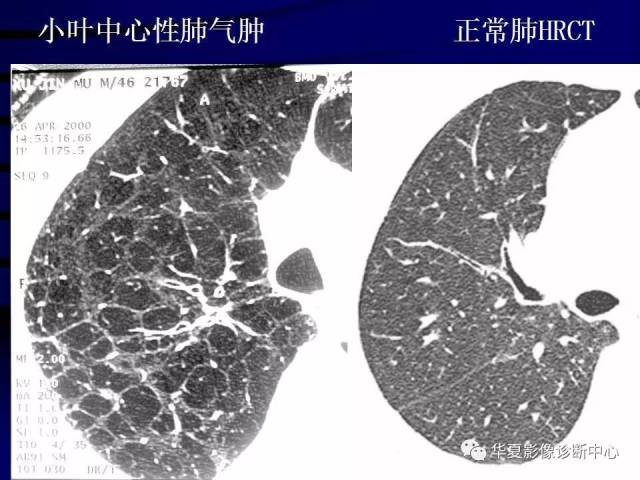

CT肺气肿分四个类型

肺气肿的ct

肺气肿的ct表现

肺气肿ct图片讲解

肺气肿的ct图片

肺气肿图片

肺气肿图片高清图片

正常肺部CT